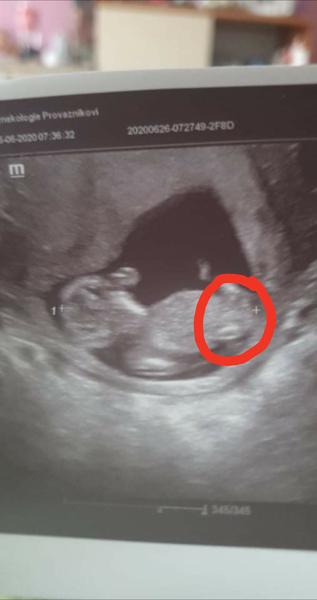

@rennye me domtor tvrdil ze je zepredu a ze ma rostazene nohy a ze az tam bude mít pohlavi tak doufa ze to ukáže stejně tak hezky jako tady ba fotce . Jedna moje známá mi poslala místo jde prý vidí kavove zrno

@lilian2111 no doktor mi to řekl uz jen mě zajímalo zda tu někdo pozná pac tady na te fotce je doktor ukázal primo kde co je a kávové zrno tam je 🙂

@lilian2111 a na fcb skupině 75 žen potvrdilo holku ze vidí

@almidrob2539 tak když to po doktorovi potvrdily ženský na fb 🙊😃

@almidrob2539 To je pořád ta samá fotka, ale zvětšená. Holka to být může, je to více pravděpodobné, ale jistá bych si tím nebyla, je to špatně vidět. Takové fotky mám i od kluků 😂.